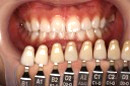

| 色を確認し、同時に比較写真を撮影します | |||||||||